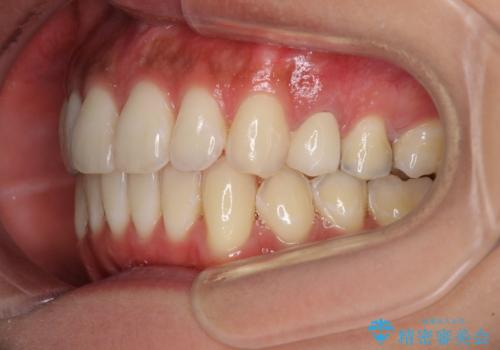

八重歯の再矯正 インビザラインでストレスなく矯正治療

- 学生の頃に矯正治療を行ったものの、保定を怠けてしまったことによる後戻りを気にして来院された患者様です。

根管治療が必要な歯があったため、矯正治療前に根管治療を行い、その後はインビザラインにより矯正治療を行うこととしました。

下顎の八重歯が上顎歯列に収まる過程で咬みにくさがありましたが、最終的には、咬み合わせも安定し、きれいに歯列を整えることができました。